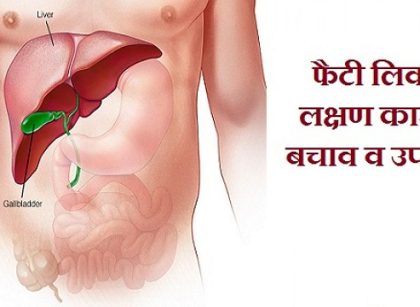

Fatty Liver: फैटी लिवर की समस्या से हैं परेशान तो इन चीजों से बना लें दूरी, मिलेगी राहत

फैटी लिवर की समस्या से पाना चाहते हैं निजात? तो बेहद काम आएंगी ये टिप्स

फैटी लिवर से हैं परेशान तो इन चीजों से बना लें दूरी, मिलेगा छुटकारा

इन लोगों के लिए जानलेवा हो सकता है फैटी लिवर! कंट्रोल करने में बेहद काम आएंगी ये टिप्स

फैटी लिवर की समस्या को करना चाहते हैं कंट्रोल तो रोजाना इन चीजों का करें सेवन

इन लोगों में होता है फैटी लिवर का ज्यादा खतरा, ये लक्षण दिखते ही हो जाएं सतर्क!

शरीर के लिए खतरनाक है फैटी लिवर, इन 4 आसान घरेलू उपायों से दूर होगी परेशानी